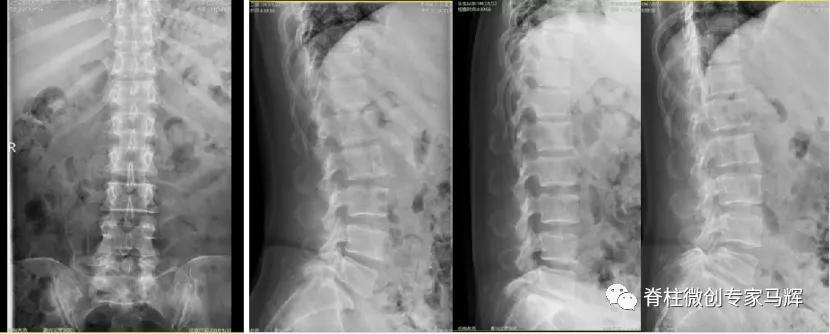

2018年腰椎术前

2018年腰椎术后

2019年腰椎内固定取出后